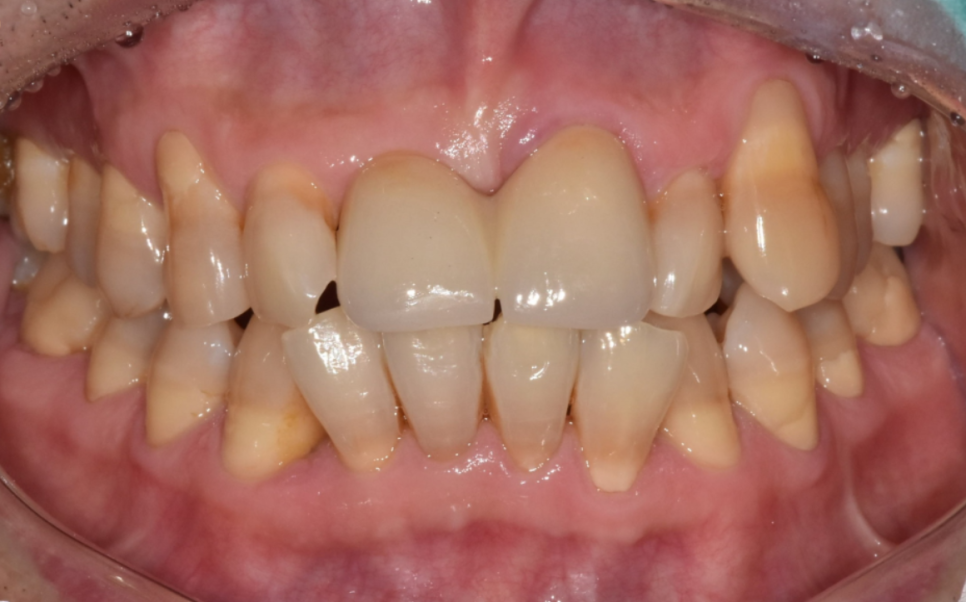

이 환자분이 저희 병원에 오시게 된 이유들은 다음과 같습니다.

230413

왼쪽 앞니가 아래로 더 내려앉는 느낌

찬 것만 먹어도 시린 증상

앞니 사이 틈이 점점 넓어지는 변화

시간이 지날수록 위의 증상이 심해져서 고민하고 계셨습니다.

입안을 확인했을 때,

해당 부위 잇몸 안쪽으로 치석이 보였습니다.

230413 잇몸 내려감으로 길어진 치아, 방치하면 안 되는 원인, 증상, 이유

정확한 상태 확인을 위해 엑스레이 촬영과 검사를 진행한 결과,

치석으로 인해 잇몸병이 진행되면서

잇몸뼈가 일부 녹아 있는 상태였습니다.

230413 / 230417

230413(전) 230515 (후)